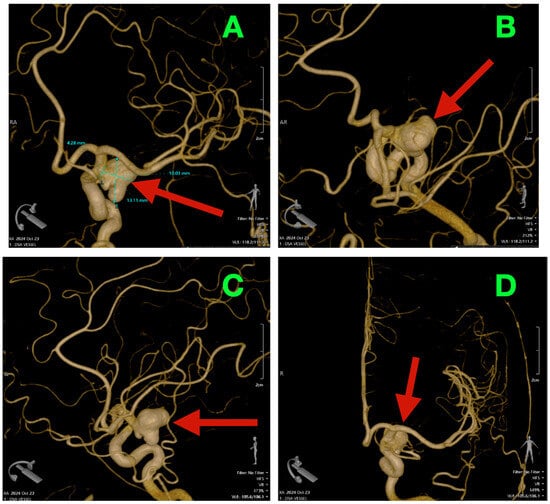

2.5. Imaging Findings and Morphometric Analysis

2.6. Preoperative Angiographic Findings